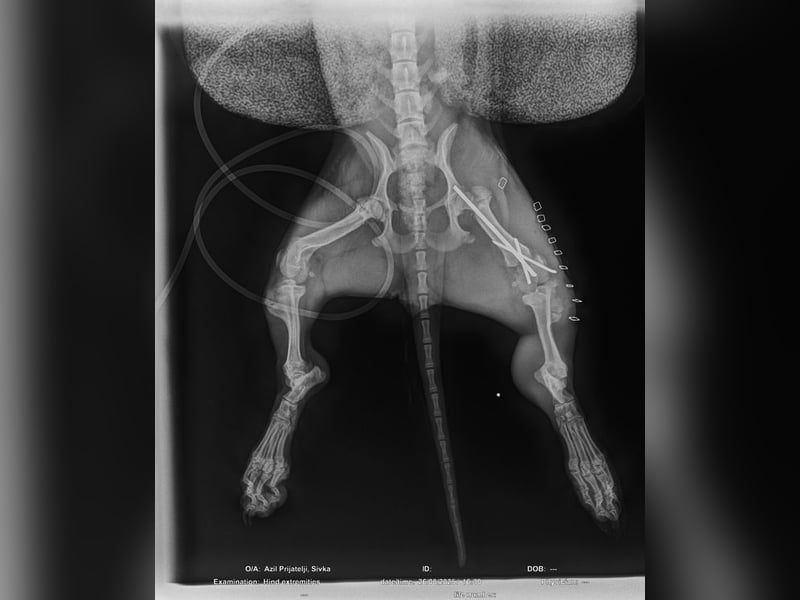

Bemerkungen: Ilse wurde von einem Auto angefahren und erlitt dabei einen Beinbruch. Weitere Informationen über den Beinbruch sind im nachfolgenden Text enthalten.

Dies hat sich dann vermutlich Ilse abgeschaut und gedacht, wenn das die Junghunde können dann kann das ein kleines und zartes Welpenmädchen auch. Leider keine gute Idee von Ilse, dann sie wurde von einem Auto angefahren und brach sich dabei einen Knochen am Hinterbein.

Ihr Frauchen bat nun unser kroatisches Partnertierheim um Hilfe bei er Operation. Die Tierheimleiterin stimmte dieser Sache zu, allerdings nur unter der Voraussetzung, dass Ilse dann im Tierheim bleiben durfte und Ilse sich dann eine neue Familie suchen darf. Ferner stellten wir die Bedingung, dass sich die zuständigen Behörden den Tierbestand der Frau anschauen und nötige Impfungen und Kastrationen durchführen darf. Die Frau stimmte diesen Bedingungen zu. Ilse wurde operiert und durfte bei der Tierheimleitung im Wohnhaus einziehen und hat sich dort zu einer richtigen kleinen Schönheit entwickelt.

Die Operation verlief erfolgreich, allerdings schont Ilse ihr Bein zur Zeit noch. Da Ilse aber noch sehr jung ist, wird dies vermutlich recht schnell heilen und Ilse wird ihr Bein auch wieder normal belasten. Die unten beigefügten Videos machen Mut und Freude.

Für den Muskelaufbau wird Ilse vermutlich etwas Physiotherapie benötigen.